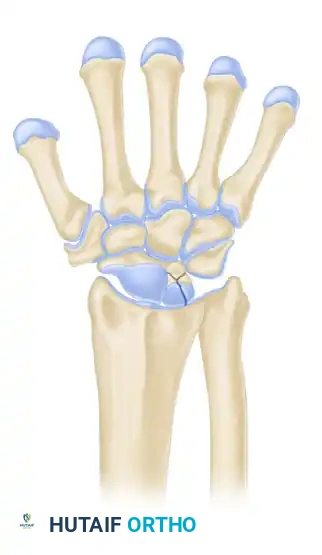

LICHTMAN CLASSIFICATION OF KIENBÖCK DISEASE

The staging classification proposed by Lichtman et al. is the universally accepted framework for guiding surgical decision-making. The natural history, if left untreated, progresses from sclerosis to fragmentation, carpal collapse, and ultimately pancarpal arthritis.

Stage IIIA

- Description: Fragmentation and collapse of the lunate occur, but carpal alignment is maintained. The scaphoid remains normally aligned.

- Treatment: Joint leveling procedures remain the gold standard if the radiocarpal joint is preserved. Revascularization procedures (pedicled bone grafts) are also utilized.